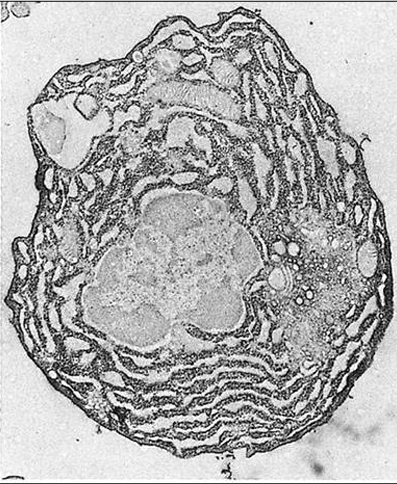

Células hematopoyéticas

Biopsia médula ósea

Valoración cantidad tejido hematopoyético/tejido adiposo

Extendido aspirado medular

Grupo medular

BIOPSIA MÉDULA OSEA Y ASPIRADO MEDULAR